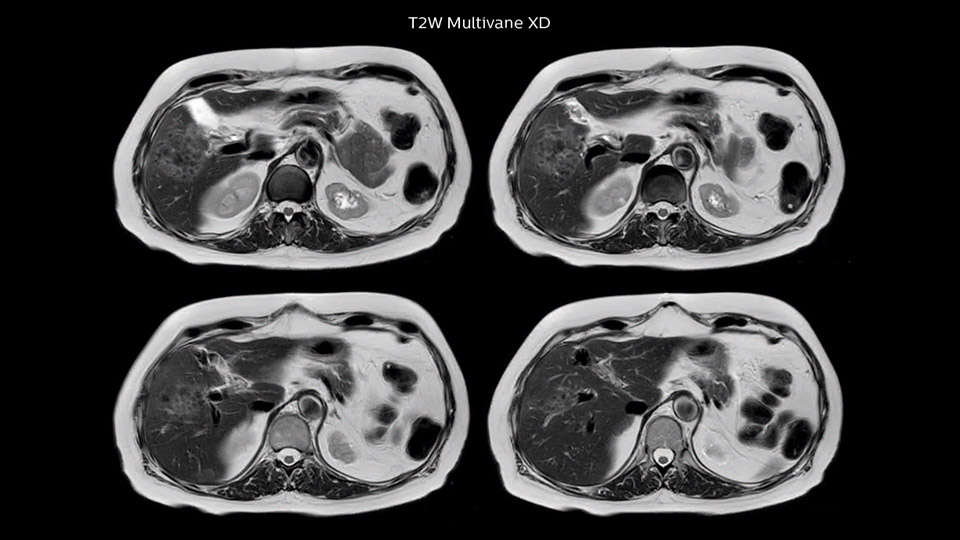

Dr. Baumann then implemented MultiVane XD for motion correction. It uses an extended reconstruction algorithm for imaging that is virtually motion free. “With MultiVane XD we get excellent motion-corrected images with high spatial resolution. We typically first optimize our scan for high image quality, and when satisfied with that, we try to reduce the scan time. So, we combined MultiVane XD with dS SENSE, which allows us to shorten the scan time,” he explains. “The performance of MultiVane XD in liver imaging is outstanding. MultiVane XD with dS SENSE is a powerful development in improving liver image quality.” “As we use breathhold imaging for T2-weighted liver scans, we depend on the patient’s ability to cooperate with the exam. This can present a real challenge when we are looking for small lesions, such as in our oncological patients. However, with MultiVane XD motion correction, we get excellent images. This is important for our surgeons, because they want to know exactly where the lesions are.”

“Our liver exams are quite fast,” says Dr. Baumann. “If the patient tolerates it, we use an arms-up position to reduce the FOV and speed up the exam with dS SENSE.” “We acquire one transversal high resolution T2-weighted sequence with 3 mm slice thickness, for example for pancreas or liver lesions. Then we also add a T2 fat suppressed MultiVane XD SPIR sequence. We perform these two routinely in our liver imaging. We use high dS SENSE factors to significantly shorten scan times to 2-4 minutes, which can improve our protocol; it’s a very robust scan.” “We include mDIXON for the dynamic sequences because of the robust and homogeneous fat suppression we get with that. We had been using eTHRIVE, but we are now quite happy with mDIXON. Sometimes we use a medication to calm the bowels, to further improve the image quality.”

“I would absolutely recommend to other sites to implement MultiVane XD with dS SENSE in their abdominal cases, as it’s brilliant for robust, motion-corrected abdominal imaging. It provides us with excellent image quality with high resolution in a short time,” says Dr. Baumann. “I would advise using MultiVane XD for T2 and T2 fat suppressed high quality imaging for almost every liver case.”